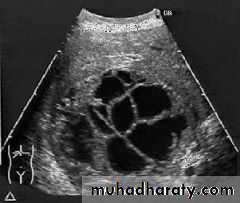

• no contrast.Gall stone & cholecystitis

Obstructive jaundice

US